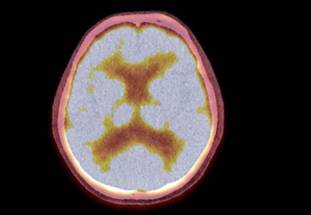

In a new study, investigators from McLean Hospital, Harvard Medical School and the National Institute on Drug Abuse—Intramural Research Program (NIDA-IRP) have discovered that the tendency of people's arousal to wane over the course of brain scans has been distorting the brain connection maps produced by functional magnetic resonance imaging (fMRI).

The team found that as people's arousal levels dwindle during an fMRI, such as if they become more relaxed and sleepy, changes in breathing and heart rates alter blood oxygen levels in the brain—which are then falsely detected on the scan as neuronal activity.

fMRI scans are commonly used to non-invasively map brain connectivity in a variety of situations, including planning for surgery, understanding the impact of a stroke, and studying how mental illness affects neurological function. However, since fMRI relies on changes in brain blood oxygen to indirectly measure neuronal activity, it is vulnerable to "noise" from other processes that can affect blood oxygen—such as changes in breathing and heart rates.

In the present study, the research team identified a specific blood flow signal that seemed to track both the decline in subject arousal levels and the illusory inflation of functional brain connection strengths. This non-neuronal, physiological noise signal—termed the "systemic low frequency oscillation" (sLFO) signal—grew over time during scanning, in a spatial and temporal pattern that tightly matched the pattern of the connection strength increases.